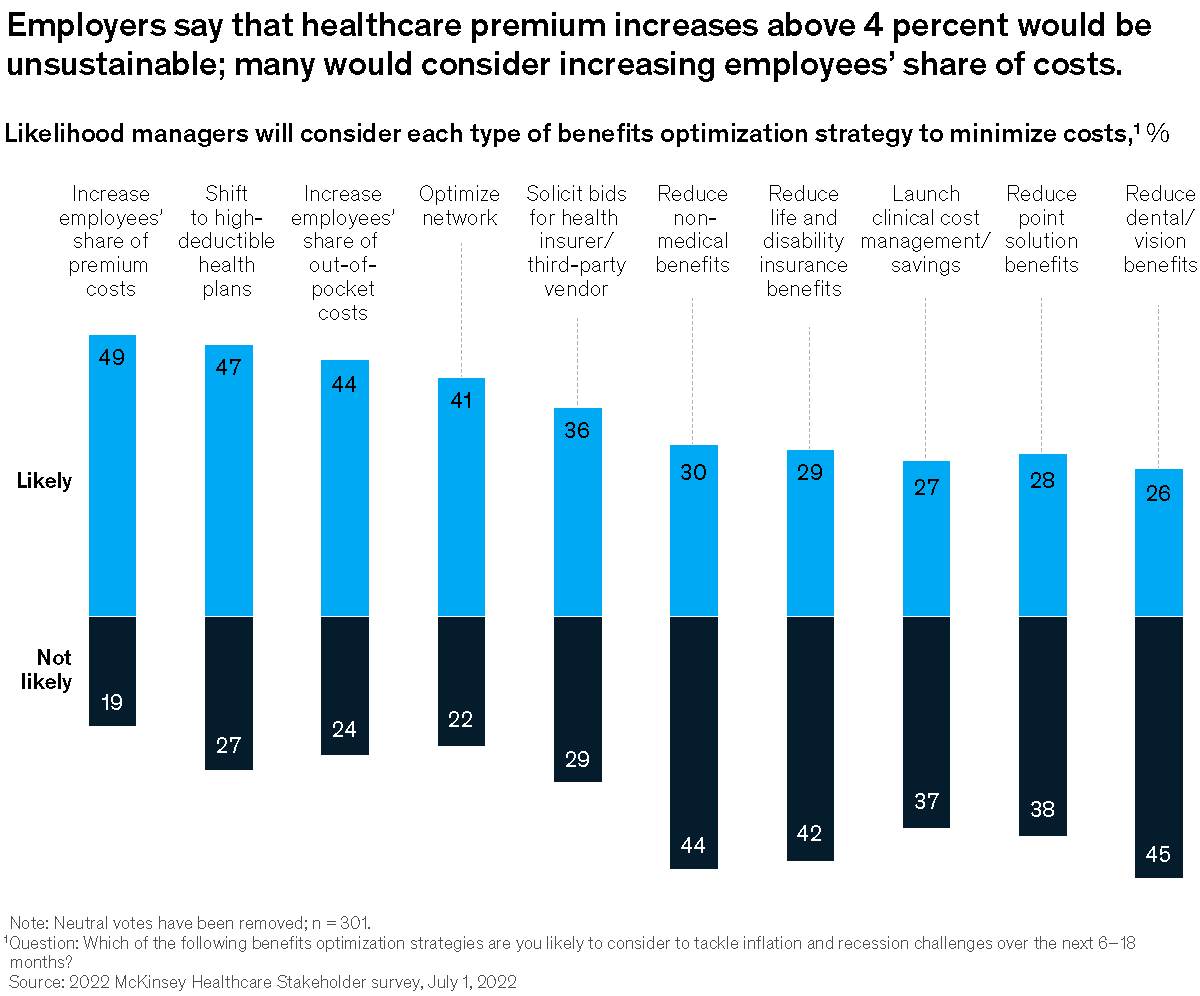

EV-charging, gender parity, and more Share these insights